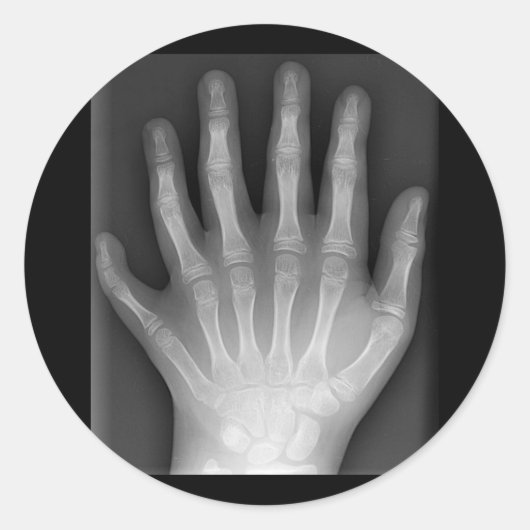

Polydactyly, Six Fingered Hand, X-Ray, zeldzaamhei Ronde Sticker

Six Fingered Hand Deze röntgenfoto, gestript van identificatiemerktekens, wordt voorgesteld door Drgnu23, een Podiatrist die werkt met de kansarmen. Hier zie je een medische zeldzaamheid. De hand van een tienjarige jongen, geboren met zes vingers. Dit afbeelding, gepresenteerd op een zwart t-shirt-shirt, zal mensen nieuwsgierig maken en verbijsterd raken door de natuur van de menselijke biologie.